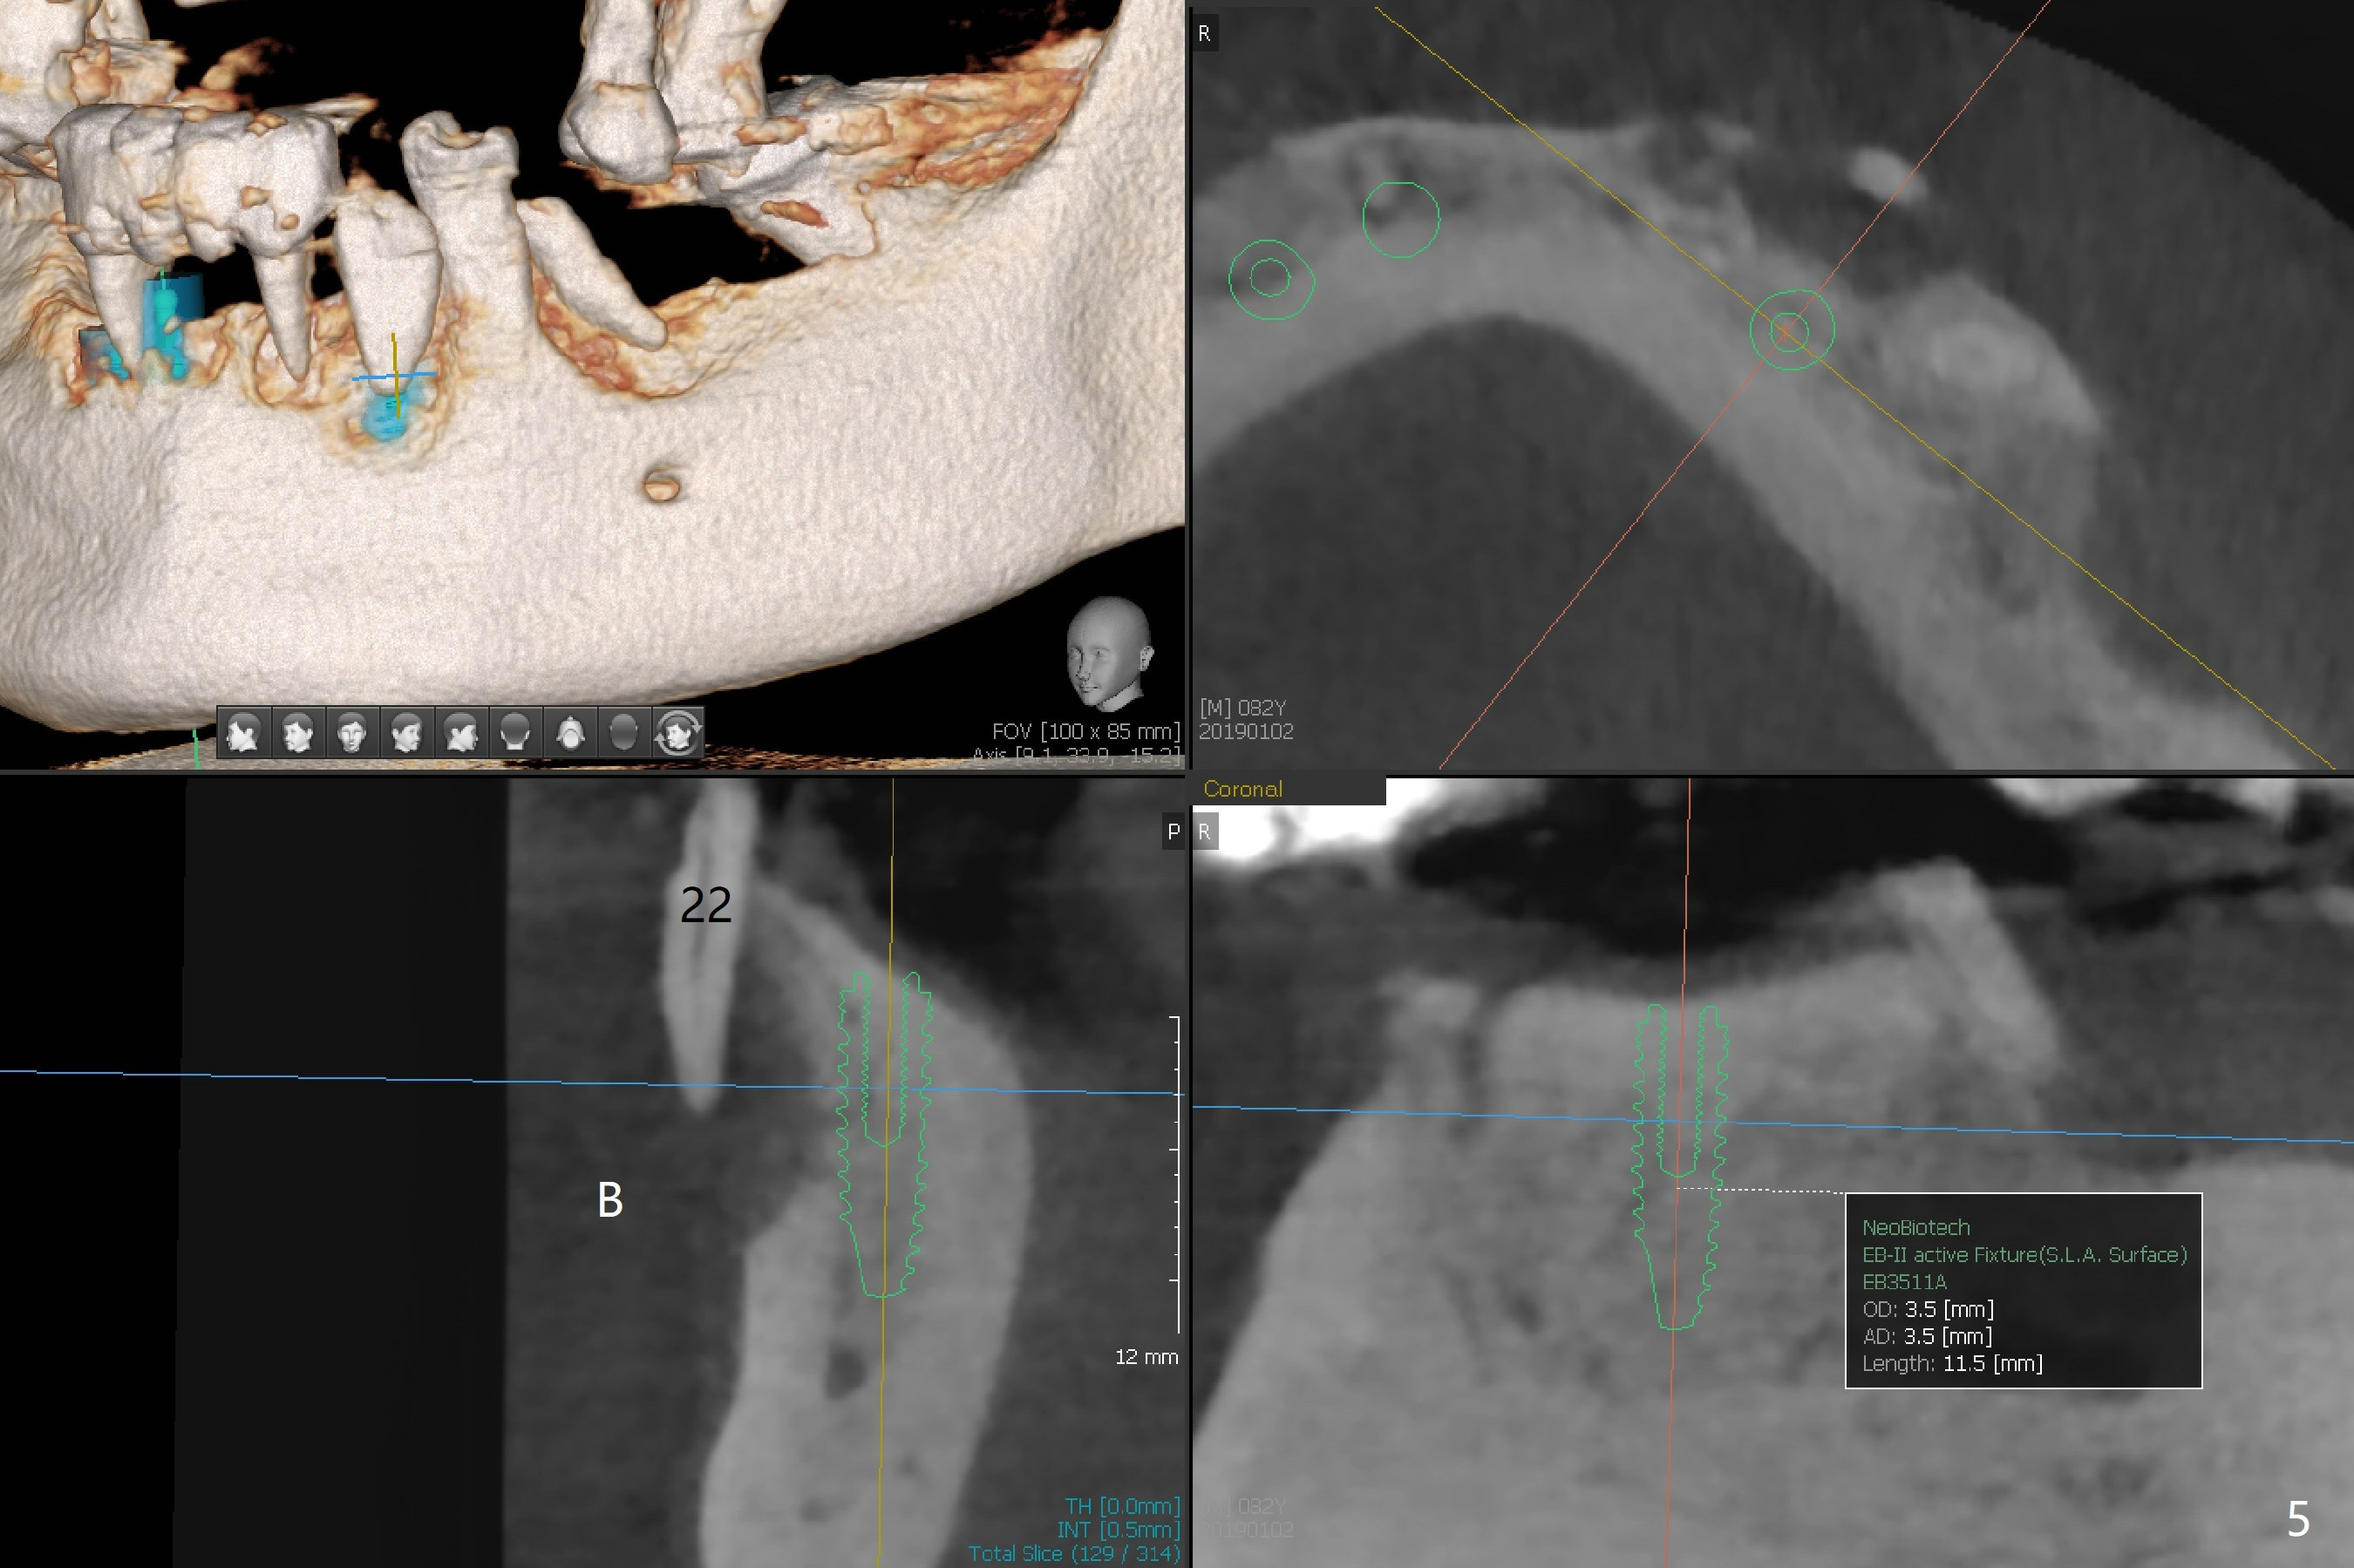

Abutments for Lower RPD

A 82-year-old man with poor dentition (upper and lower RPDs) returns to clinic for definitive treatment 2 weeks post socket preservation at #27 (with loss of the buccal plate, Fig.1). The bridge at #23-26 is mobile and to be removed. The tooth #22 appears to be restorable, but there is a buccal fistula (Fig.2 *). The root is out of the socket revealed by CBCT (Fig.5). Bone loss is severe at #20 (Fig.1,6). Three implants are going to be placed with guide at 27 or 26, 22 and 20 (Fig.3-6) with ball abutments for the lower RPD retention. Later the tooth #18 is found to be nonsalvageable.